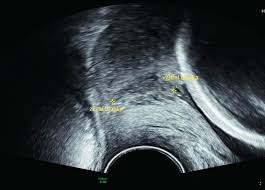

Cervical Length Scan

- Done via transvaginal ultrasound

- Measures cervix length

- A short cervix increases risk of preterm birth